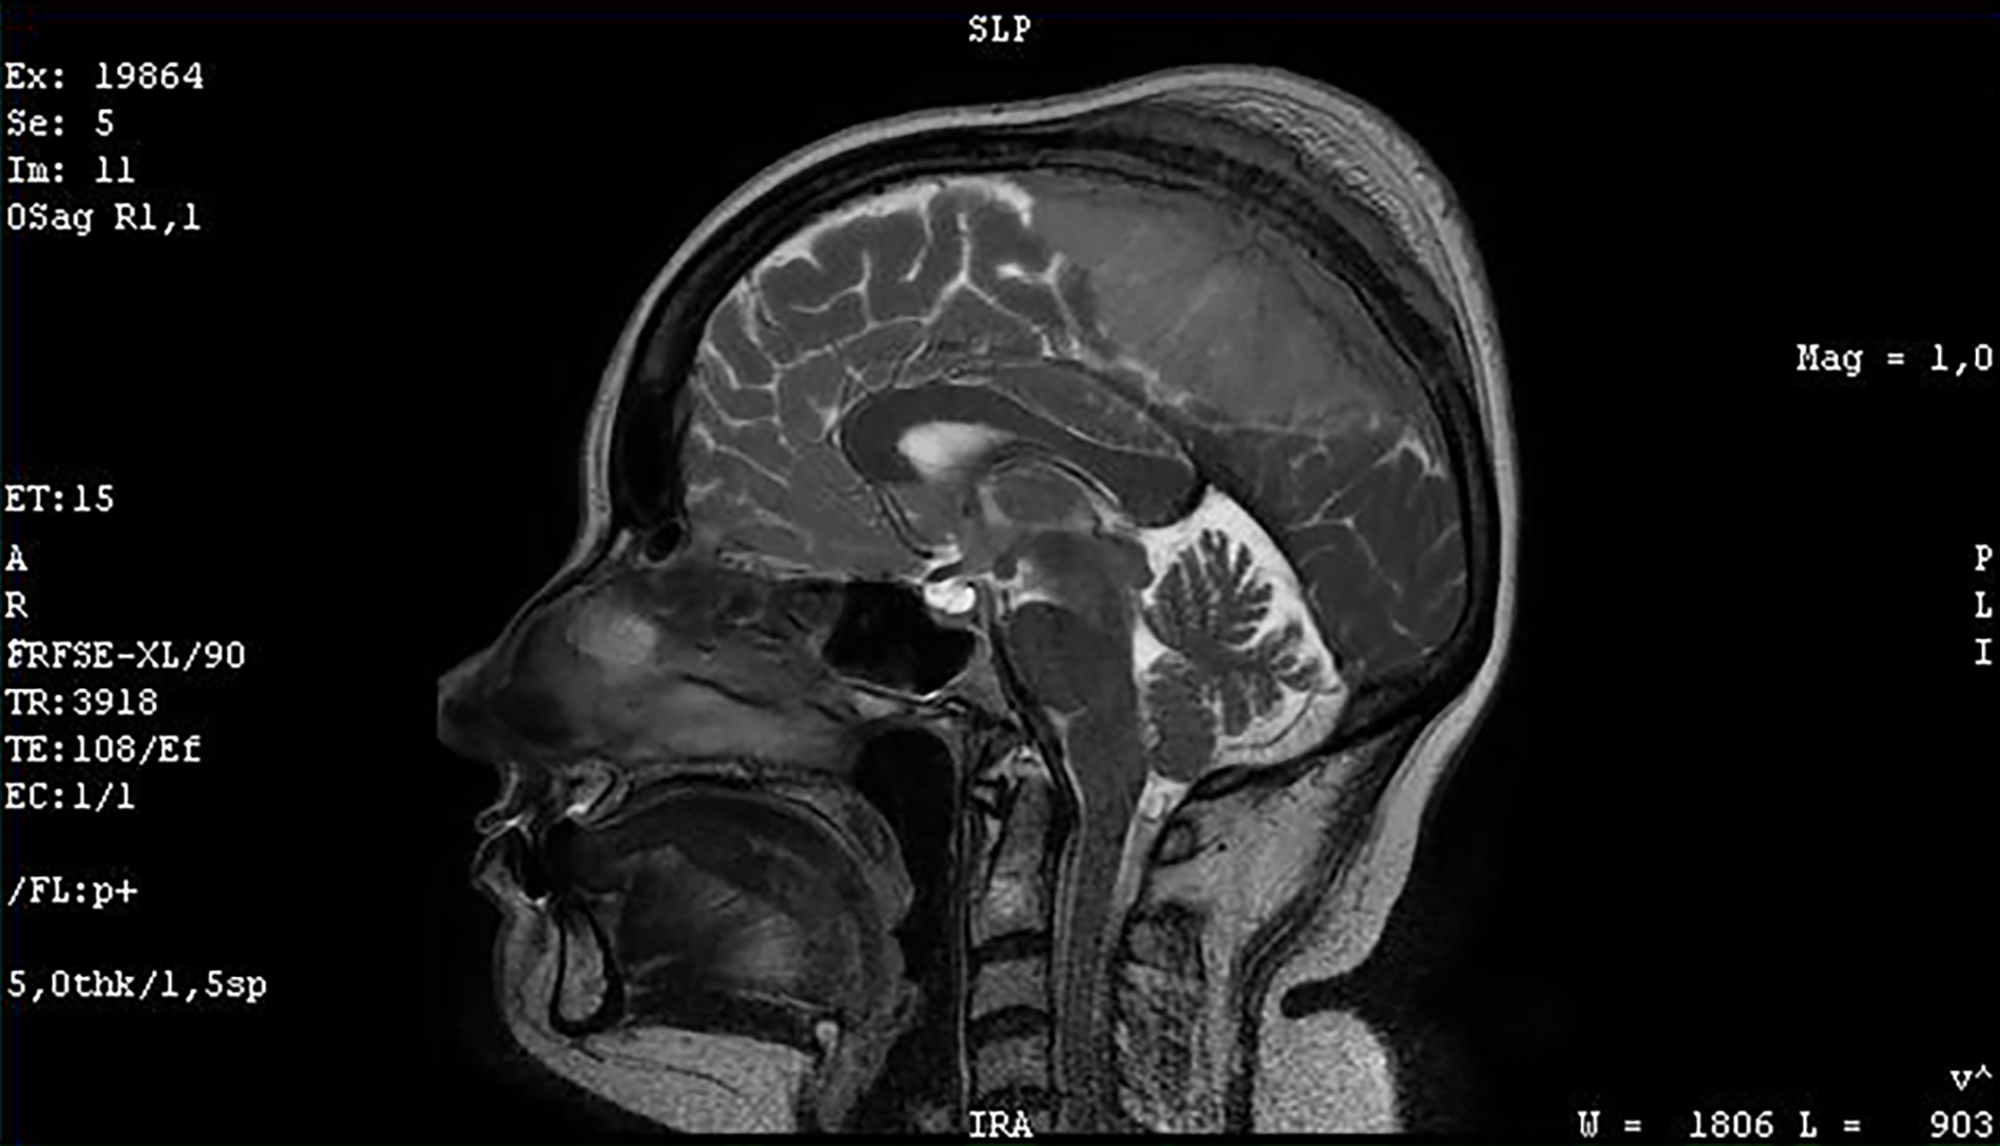

5. 1. 영상 검사

의학 영상은 뇌종양 진단에 핵심적인 역할을 한다. 초기에는 침습적이고 위험한 방법들이 사용되었지만, 현재는 비침습적이고 고해상도 기술인 자기 공명 영상(MRI)과 컴퓨터 단층 촬영(CT) 스캔이 주로 사용된다.[42]| 검사 종류 | 설명 | 특징 |

| 자기 공명 영상(MRI) | 뇌종양 진단에 가장 선호되는 영상 검사이다.[24][43] | 교모세포종은 T1 강조 MRI에서 조영 증강, T2 및 FLAIR 영상에서 고신호 뇌부종을 보인다.[24] 저등급 신경교종은 T1 MRI에서 저신호, T2 및 FLAIR MRI에서는 고신호를 보인다. 수막종은 MRI에서 경막 비후와 함께 균일하게 조영 증강된다.[24] |

두개인두종은 석회화가 자주 관찰된다. 수막종도 석회화를 동반하며, 조영 증강 컴퓨터 단층 촬영(CT) 또는 자기 공명 영상(MRI)에서 균일한 조영 증강 효과를 보인다. 신경교종은 뇌 실질과의 경계가 불분명하고, 조영 시 불균일한 농염상 또는 링 엔핸스먼트가 관찰된다. 뇌 농양과 전이성 뇌종양도 링 엔핸스먼트가 나타날 수 있다. 악성도가 낮은 신경교종은 조영 효과가 낮다.